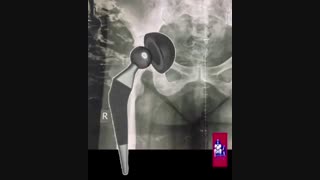

جراحی تعویض کامل مفصل لگن از طریق برش قدامی